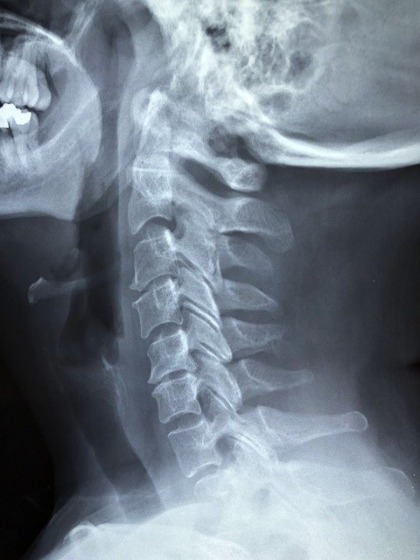

追突事故などで神経根が障害を受けている場合に実施され、頚椎捻挫などと診断された場合は、スパーリングテストで神経根の状態を確認します。

首から上腕の外側に痛みがある場合は第5頚髄神経、首から上腕前腕に痛みがある場合は第6頚髄神経に、障害が受けていると考えられます。

首から上腕の後ろ側、中指にかけて痛みがある場合は第7頸髄神経、内側の小指にかけて痛みがある場合は第8頚髄神経に、障害が出ていると考えても良いでしょう。